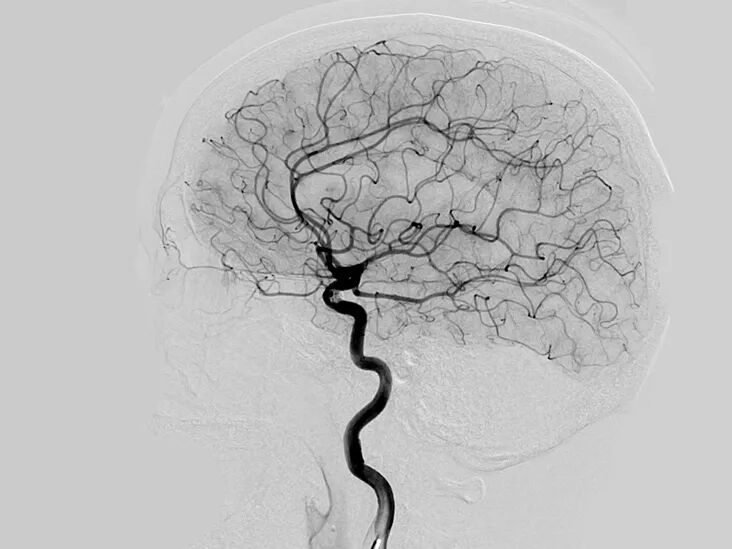

△ 血管造影术(angiogram)拍到的脑部血管。 血管造影术是利用X光观察血管堵塞的医学方法。